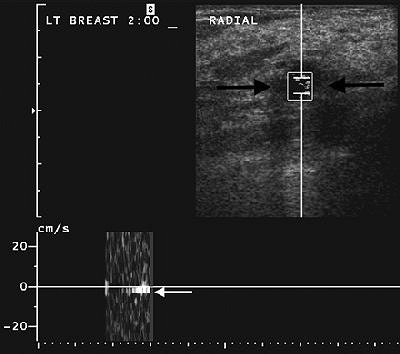

![]() |

| Same patient as above. After one acquisition, streaming detection sonogram shows same cyst with Doppler cursor positioned over cyst (black arrows). Resulting Doppler wave signal shows acoustic streaming seen as white band below baseline (white arrow), indicating fluid-filled lesion. Lesion was confirmed as cyst at aspiration. Soo MS, Ghate SV, Baker JA, Rosen EL, Walsh R, Warwick BN, Ramachandran AR, Nightingale KR, "Streaming Detection for Evaluation of Indeterminate Sonographic Breast Masses: A Pilot Study" (AJR 2006; 186:1335-1341). |

Streaming detection was positive for fluid movement during at least one acquisition, producing a sensitivity of 50% and PPV of 100% for cysts.